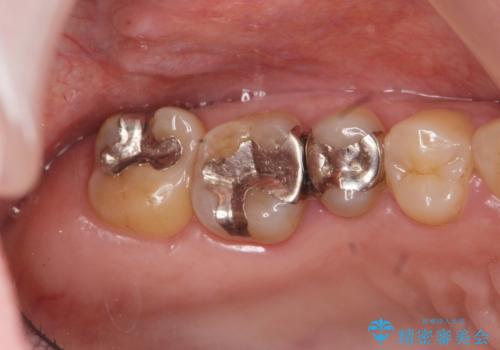

再生治療、歯周外科を行うことで歯周病治療を行い、残すことのできる歯の歯周環境を整える。

治療期間はかかりましたが、しっかりと歯周病治療・インプラント治療を行ったおかげで歯周病の状態は非常に良くなり、安定した咬合関係を確立することができました。